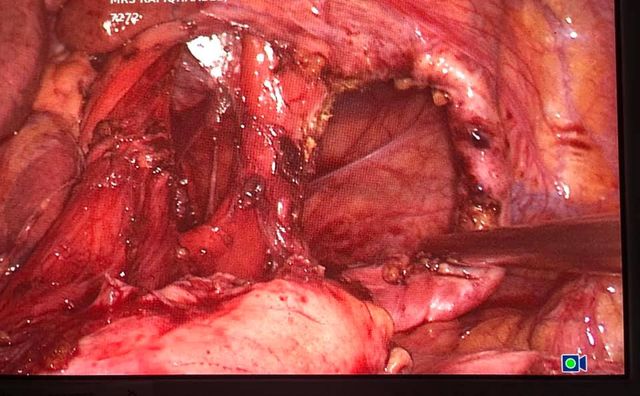

ALLPS hepatectomy 45 year old child’s A cirrhosis with normal LFT and no portal hypertension.

Interesting images October: ALLPS hepatectomy 45 year old child’s A cirrhosis with normal LFT and no portal hypertension. Planned for a right hepatectomy however intraoperative portal vein pressure was 13 mm ( preferably less than 8 mm) so altered strategy and did ALLPS (Associating Liver Partition and Portal vein Ligation for Staged hepatectomy) In ALLPS stage 1 we ligate portal vein, transect parenchyma fully by hanging and mobilise the right lobe fully. (Image 1,2 and 3) 7 to 10 days (8th day in our Pt)later depending on LFT trend we document the hypertrophy on CT scan and do the completion hepatectomy (pics . Although it has its own shortcomings in selected patients (like in our case ) it has been proven to achieve better degree of hypertrophy compared to Portal vein embolisation / portal vein ligation. Ideally useful for trisectionectomies.